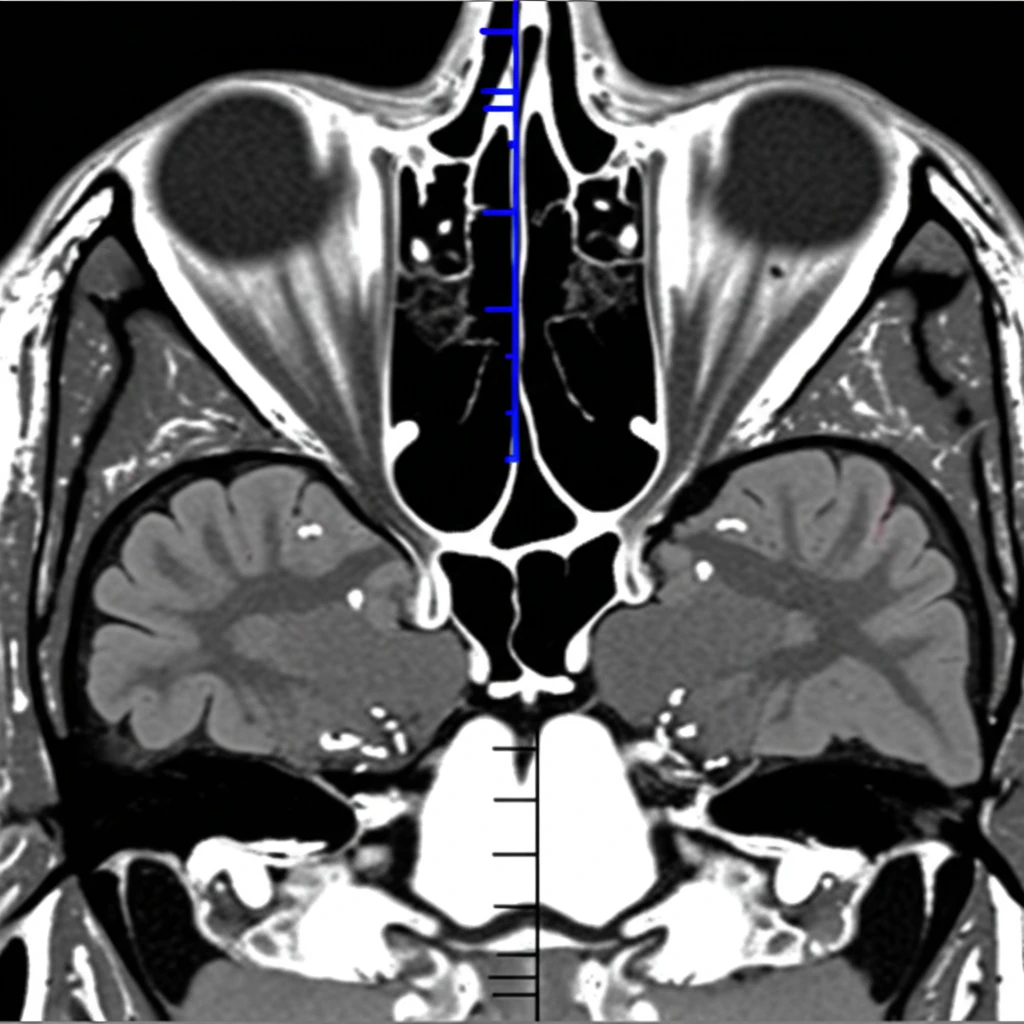

- 영상 검사: CT나 MRI를 통해 코, 부비동, 뇌의 구조적 이상(종양, 염증 등)을 확인합니다.